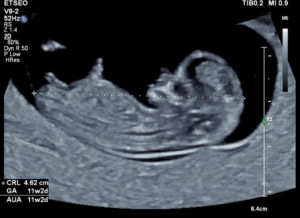

Termijnecho 10 – 12 weken

Bij deze echo wordt de termijn van de zwangerschap definitief vastgesteld. We meten de baby van kop tot stuit op. We bekijken of de ontwikkeling van de baby normaal verloopt. We meten hoe snel het hartje klopt en vaak is de baby al lekker actief in je buik aan het bewegen (maar dit voel je nog niet). Wist je dat je baby al helemaal compleet is bij 10 weken zwangerschap? Alles is al aangelegd, je baby hoeft enkel nog te groeien! Dit is ook mooi terug te zien tijdens deze echo. Wat een verschil ten opzichte van de vorige echo! Ook bij deze echo is het verzoek om met een volle blaas te komen.